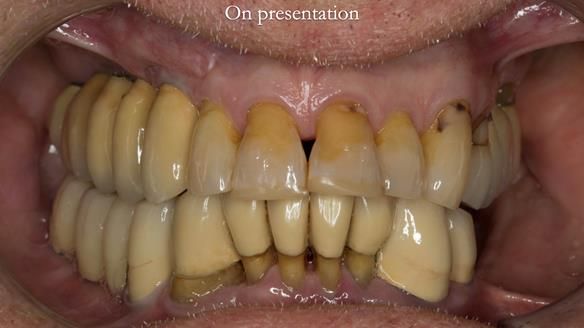

This case was always about function, not aesthetics.

Ken’s teeth were never going to look perfect.

There were stained composites, old restorations, and obvious wear.

That was accepted from the outset.

The way Rowan lengthened the teeth — particularly in the upper RPD — to match the existing gingival recession on the remaining teeth was superb. The dentures sit naturally within the context of the rest of the mouth.